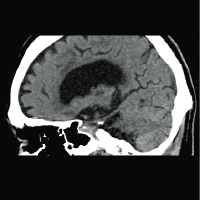

Для снижения лучевой нагрузки и повышения качества визуализации в КТ SUPRIA используются алгоритм интеллектуального перераспределения дозы IntelliEC и современный метод итерации IntelliIP, позволяющие провести сканирование с очень низкими значениями доз и получить изображения необходимого диагностического качества. В результате лучевая нагрузка на исследуемую область существенно снижается при сохранении высокого качества визуализации, особенно на уровне плотных паренхиматозных органов.